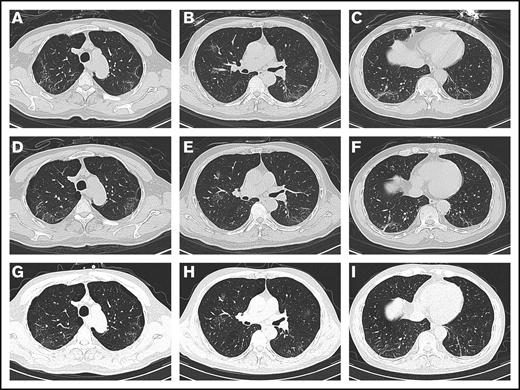

On admission, the patient’s arterial oxygen saturation increased to 96% with oxygen supplementation via nasal cannula (3 L/min). Chest CT imaging on hospital day 2 showed bilateral, multiple ground-glass opacities (Figure 1A-C). Considering his sustained chest tightness and shortness of breath, 40 mg of methylprednisolone, administered IV daily, was given on days 2 to 6. The patient then reported that his breathing had improved, but he still felt chest tightness. Chest CT imaging on hospital day 8 showed that the bilateral, multiple ground-glass opacities from the first scan remained (Figure 1D-F), and laboratory investigations revealed a high level of serum IL-6. On hospital day 9 (illness day 24), the patient was given 8 mg/kg tocilizumab, administered IV, 1 time. On hospital day 12, his chest tightness disappeared. After tocilizumab administration, the IL-6 level decreased gradually over the following 10 days (from 121.59 to 20.81 pg/mL), then increased rapidly to the peak (317.38 pg/mL), and then decreased to a low level (117.10 pg/mL) (Figure 2). The transient rebounding of the IL-6 level to the peak does not mean COVID-19 relapse: instead, this might be attributed to the recovery of the normal T cells. On hospital day 19, the patient had a third chest CT scan, which showed that the range of ground-glass opacities had obviously decreased (Figure 1G-I). The patient was declared to be cured and was discharged from the hospital on 13 March 2020. He had no symptoms of MM, and related laboratory findings were all in normal ranges (Table 1).

Chest CT images. (A-C) Chest CT imaging on hospital day 2 showed bilateral, multiple ground-glass opacities. (D-F) Chest CT imaging on hospital day 8 showed that the bilateral, multiple ground-glass opacities from the first scan were still there. (G-I) Chest CT imaging on hospital day 19 showed that the range of ground-glass opacities had obviously decreased after use of tocilizumab.